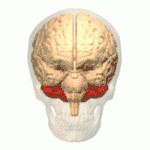

O tronco cerebral fica abaixo do cérebro e consiste no mesencéfalo, ponte e medula. Situa-se na parte posterior do crânio, repousando na parte da base conhecida como clívo, e termina no forame magno, uma grande abertura no osso occipital. O tronco cerebral continua abaixo dele como a medula espinhal, protegida pela coluna vertebral.[36]

Dez dos doze pares de nervos cranianos emergem diretamente do tronco cerebral.[36][36] O tronco cerebral também contém muitos núcleos de nervos cranianos e de nervos periféricos, bem como núcleos envolvidos na regulação de muitos processos essenciais, incluindo respiração, controle dos movimentos oculares e equilíbrio.[37][36] A formação reticular, uma rede de núcleos de formação mal definida, está presente dentro e ao longo do tronco cerebral.[36] Muitos tratos nervosos, que transmitem informações de e para o córtex cerebral para o resto do corpo, passam pelo tronco cerebral.[36]